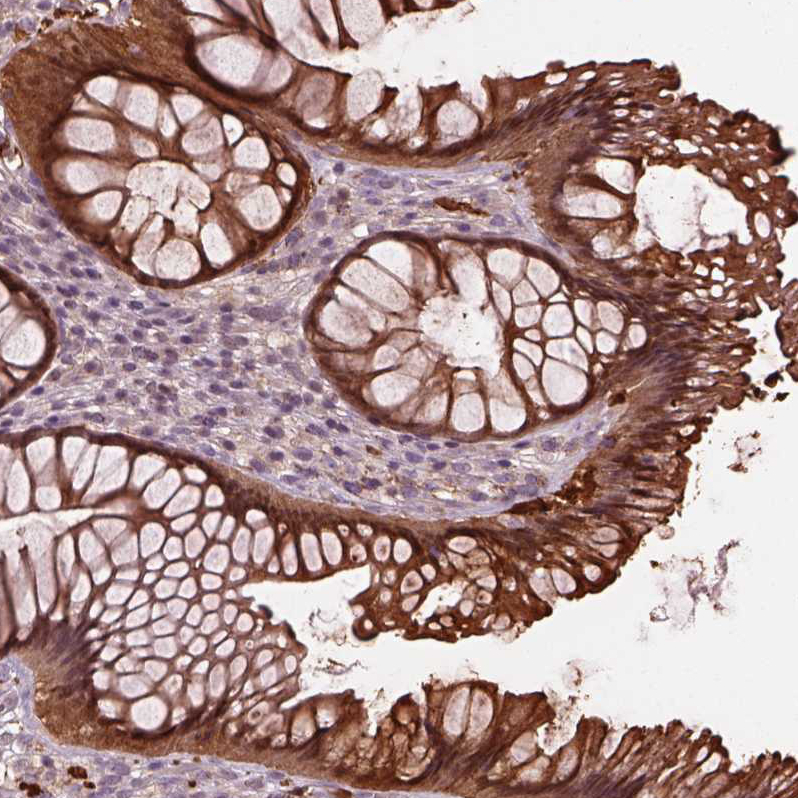

Immunohistochemistry analysis in human rectum and skeletal muscle tissues using HPA019004 antibody. Corresponding SRI RNA-seq data are presented for the same tissues.